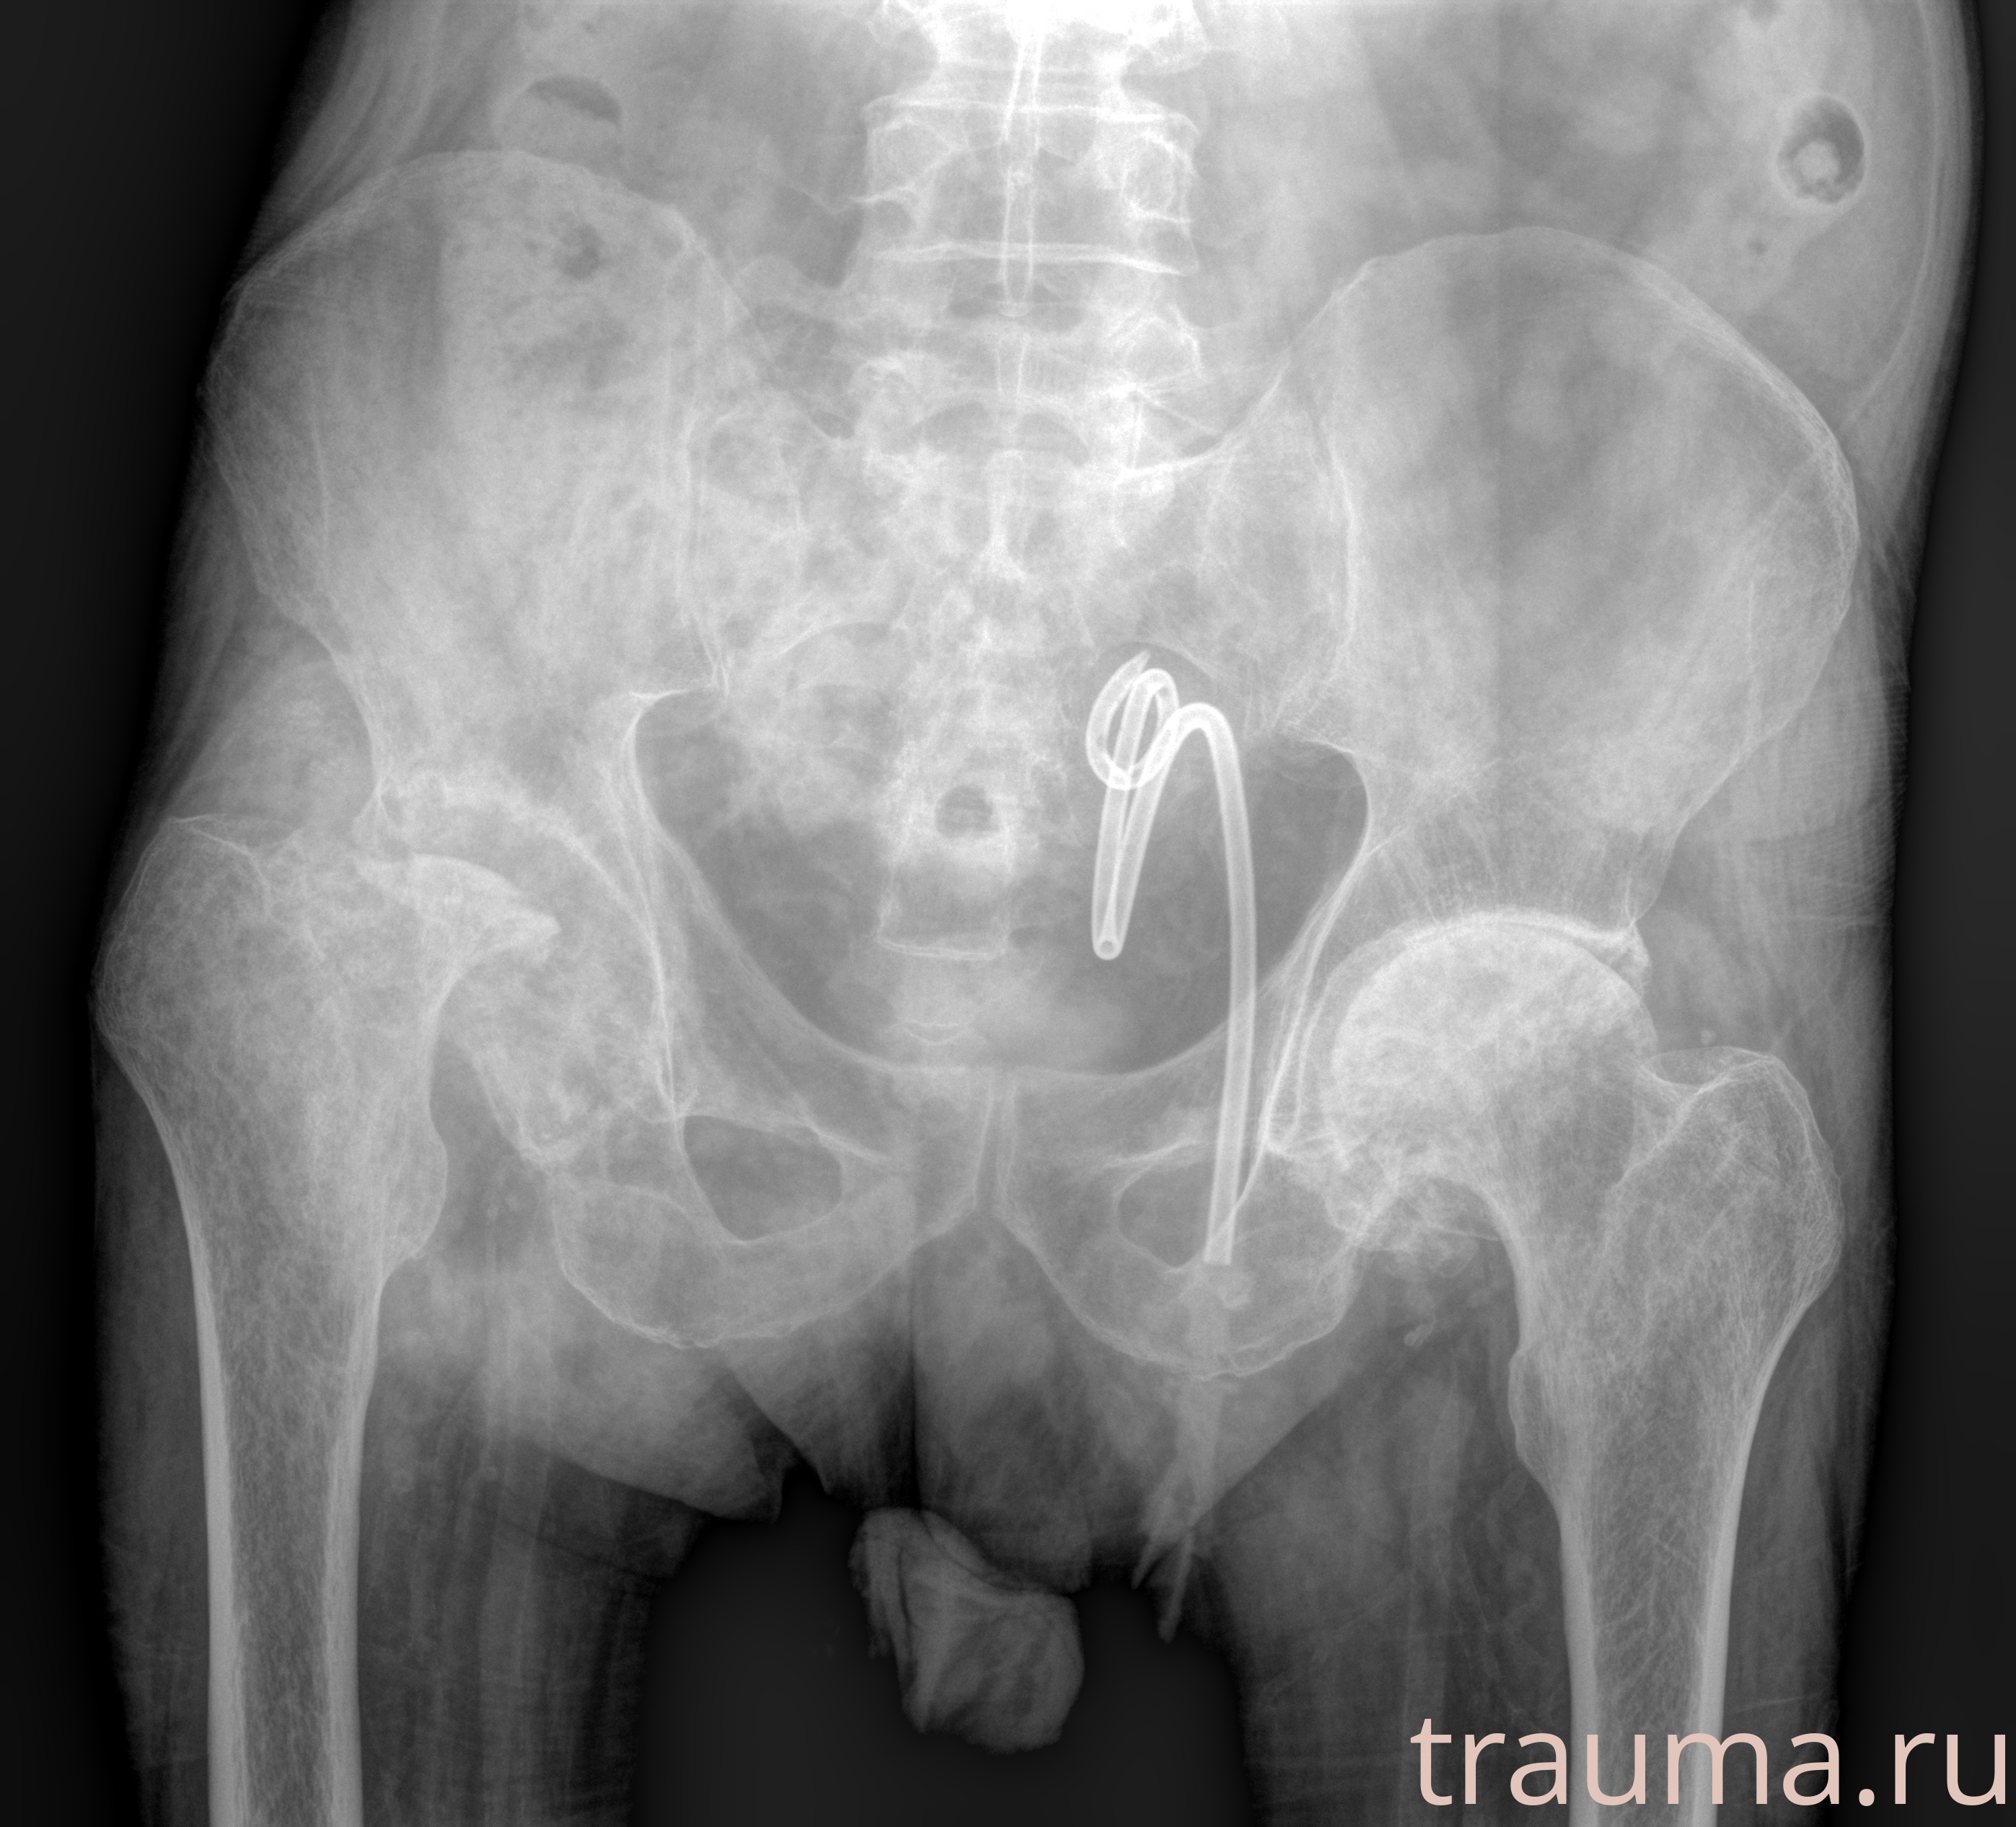

Рентгенограммы

Рентген на дому: по вашему адресу приезжает врач-рентгенолог, травматолог-ортопед с мобильным рентгеновским аппаратом, проводит диагностику травмы или заболевания, делает необходимые рентгенограммы, дает рекомендации по дальнейшему лечению. Получить качественные снимки в домашних условиях возможно благодаря уникальной методике, разработанной МосРентген Центром для института  Склифосовского